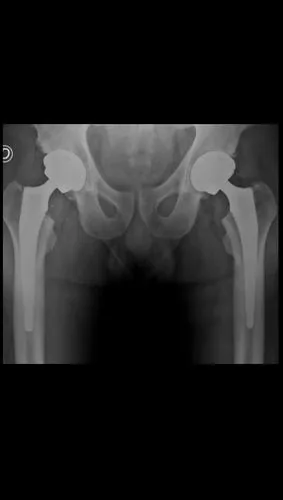

Postoperatorio

Artroplastia total bilateral de cadera en un solo tiempo quirúrgico. Alta hospitalaria a las 24 horas, deambulando con andador. Excelente restauración de la biomecánica articular bilateral.